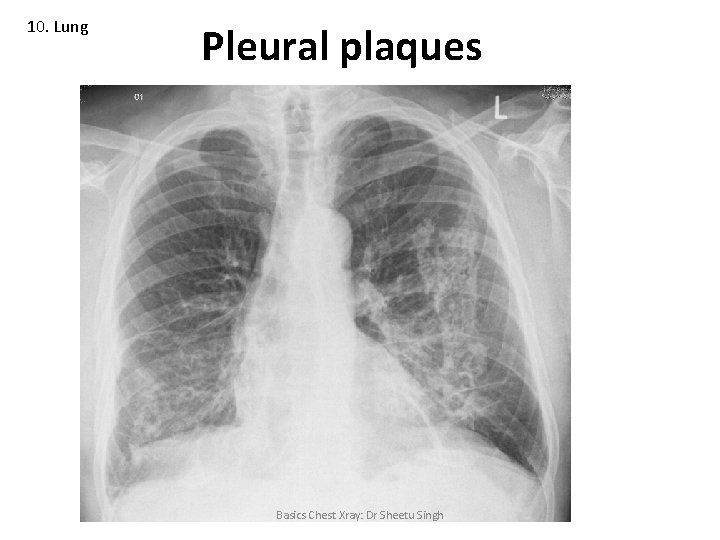

10. Lung Asbestosis • Pleural plaques (primarily the diaphragmatic pleura) • Pulmonary fibrosis • Mesothelioma • Lung cancer Basics Chest Xray: Dr Sheetu Singh

10. Lung Pleural plaques Basics Chest Xray: Dr Sheetu Singh